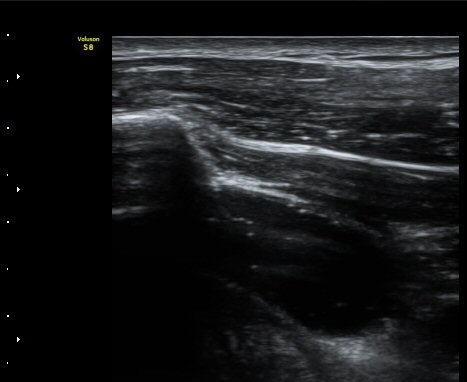

ÀÌµÎ¹Ú±Ù°Ç È¾´Ü¸é°Ë»ç¿¡¼­ °ÇÁÖÀ§¿¡ ¼Ò·®ÀÇ ¼ö¾×Àú·ù¿Í Á¡¾×³¶³» ¾×Àú·ù°¡ °üÂûµÈ´Ù(»çÁø 1, 2).

ŽÃÊÀÚ¸¦ ¾à°£ ´Ù¸®ÂÊ, ³»ÃøÀ¸·Î À̵¿ÇÏ´Ï °ß°©ÇÏ±Ù°Ç Ç¥Ãþ¿¡ ¸¹Àº ¾çÀÇ ¼ö¾×Àú·ù°¡ °üÂûµÈ´Ù(»çÁø 3).